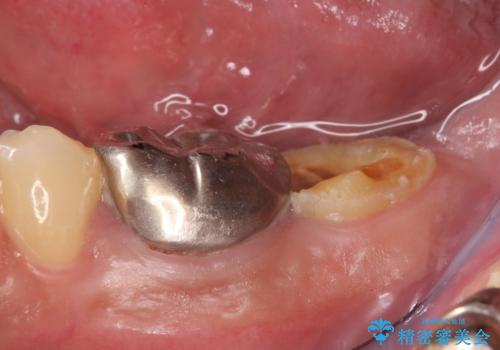

左下に被せ物を被せるクリアランス(補綴のための上下のスペース)ないため、十分な歯冠長を確保するため歯冠長延長術を行いました。

歯冠長延長術とは歯肉弁根尖側移動術とも言い、歯の高さが低くクラウン(被せ物)による治療が難しい場合に、歯茎を歯根方向に下げることで歯の高さを確保する手術です。歯の高さが十分にあることで、外れにくいしっかりとしたクラウンを被せることができます。